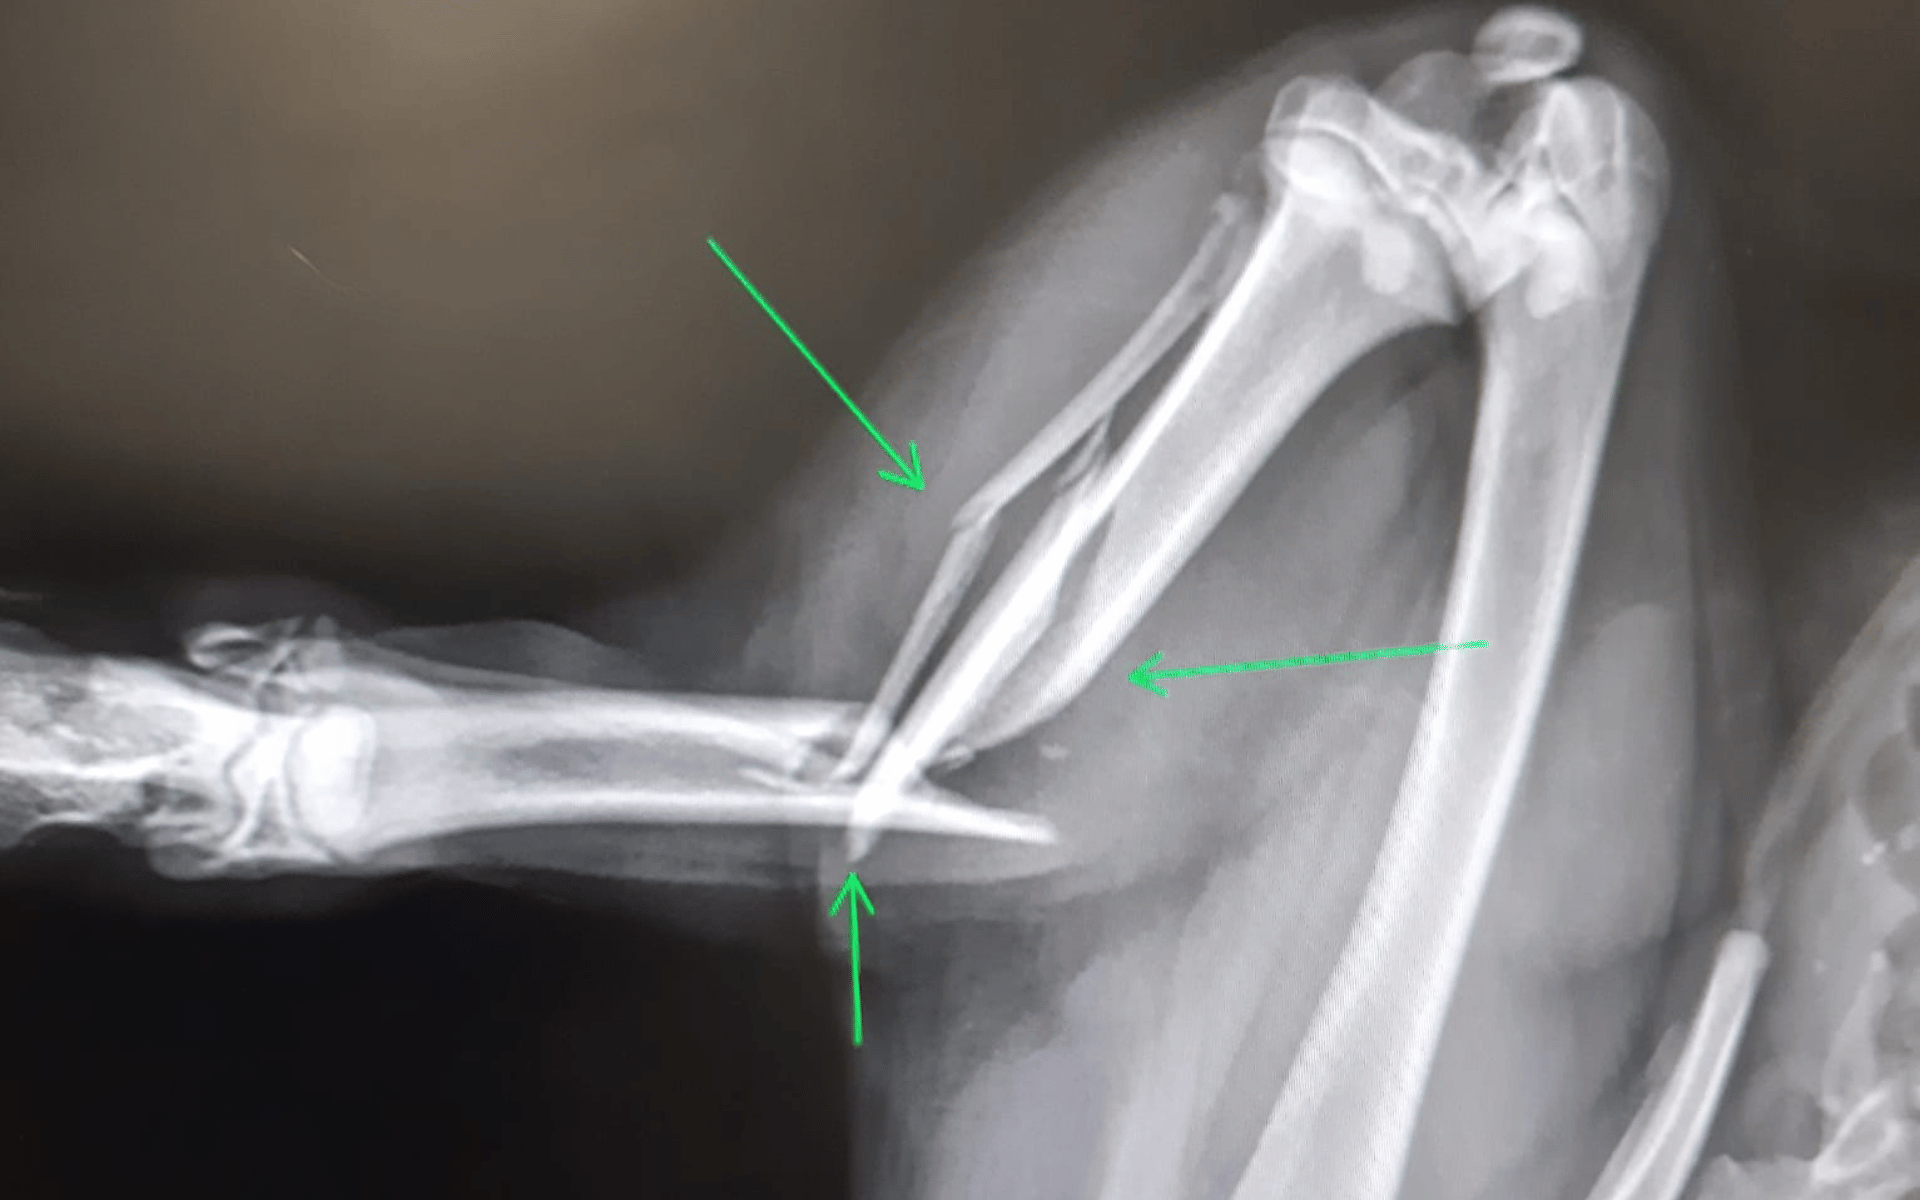

Während Damian mit anderen Hunden über den Hof tollte, hörte man plötzlich lautes Gebell und einen schrillen Schrei. Kurz darauf begann der kleine Kerl stark zu humpeln. Tierschützerin Monica brachte ihn sofort in die Klinik, wo nach dem Röntgen klar wurde: Sein Bein ist kompliziert gebrochen.

Bereits am nächsten Tag wurde Damian operiert. Um das Bein zu stabilisieren, musste ein Fixateur externe eingesetzt werden, den er nun mindestens zwei Monate tragen muss. Eine lange Zeit für einen jungen Hund – doch er zeigt sich tapfer und hat gute Chancen, wieder vollständig gesund zu werden.